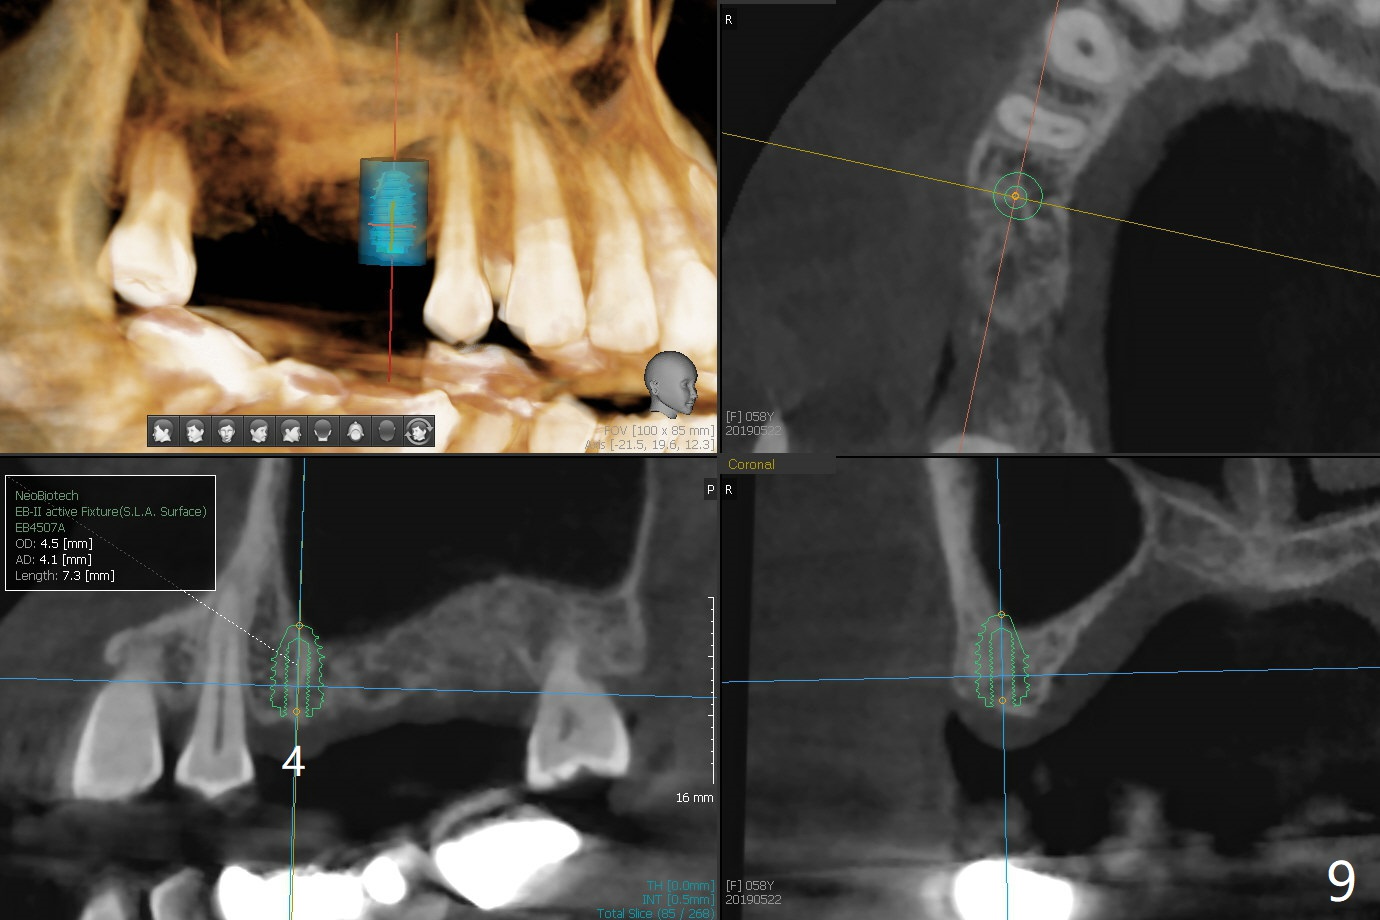

A 57-year-old woman returns with pain in the upper right quadrant (Fig.1,2). In fact the mesiobuccal root of the tooth #2 has vertical fracture. Although the socket destruction at #3 is not as extensive as that of #2, the socket of #3 has communication with the sinus. Prior to socket preservation, a piece of Osteogen plug is inserted at #3. PRF should be prepared for severe bone loss. In contrast there is no bone loss around the implants at #19 or #30 (Fig.1,3,4). Although the socket at #2 is slightly open 9 days postop, bone graft appears to be present (Fig.5). The bone at #2 and 3 seems to regenerate 7 months post socket preservation (Fig.6). Three short implants seem to be better than 2 implants for 3-unit FPD (Fig.7-9).